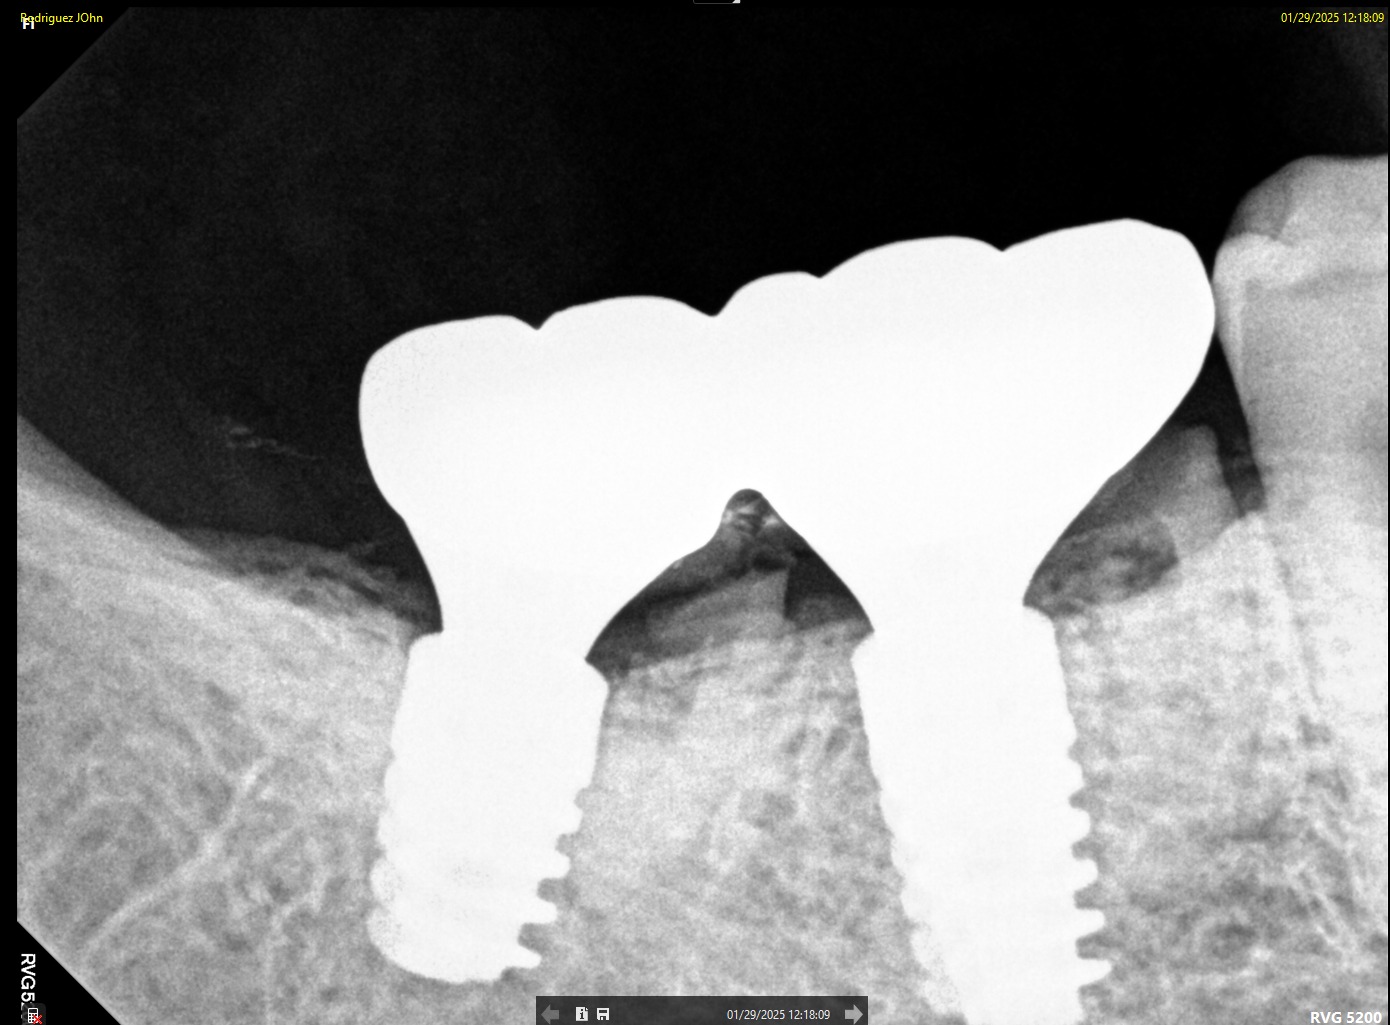

FOLLOW-UP - 2025

At the two-year follow-up:

• Continued soft tissue stability was observed

• No signs of peri-implant bone loss

• Prosthetic components remained intact and functional

Radiographic analysis confirmed long-term osseointegration and biological stability.